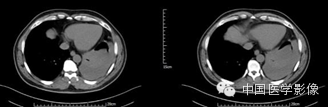

平扫

动脉期

静脉期

延迟期

【病理结果】

孤立性纤维性肿瘤